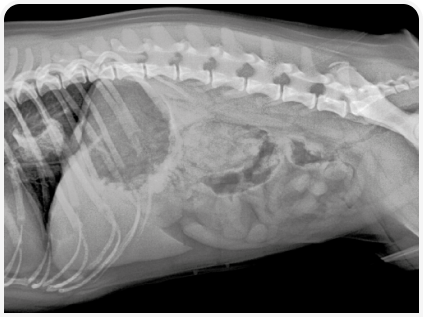

Кобель породы мопс в возрасте 11 месяцев поступил в ветеринарную клинику в связи с острой анорексией и регургитацией, которые развились за 3 дня до этого. Результаты клинического осмотра и исследования крови не выявили каких-либо существенных отклонений. При рентгенографическом исследовании грудной клетки было обнаружено затемнение в области дистального отдела пищевода, что указывало на наличие инородного тела, предположительно кости (Рисунок 1). Результаты эндоскопического исследования пищевода показали расширение пищевода в области краниального отверстия грудной клетки, а также внедрение кости в стенку пищевода краниальнее кардиального отверстия (Рисунок 2). Попытки извлечь инородное тело с помощью эндоскопии не принесли результата, хотя положение пациента меняли несколько раз. Впоследствии инородное тело сместилось в желудок. Результаты дальнейшего эндоскопического исследования не показали каких-либо патологических изменений в желудке, однако из-за тяжелых некротических язвенных поражений пищевода и возможного риска его перфорации через два дня была проведена гастротомия для извлечения кости. Затем в течение 10 дней проводилось лечение с введением омепразола, сукральфата, антибиотика и метилпреднизолона. Так как могла развиться послеоперационная стриктура, то в случае персистирования клинических симптомов было запланировано эндоскопическое исследование, однако выздоровление прошло без осложнений, и спустя год клиническое состояние собаки было удовлетворительным.